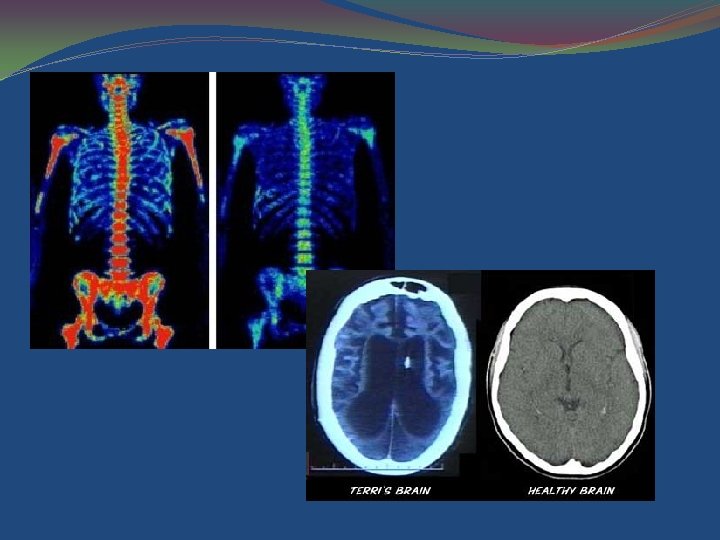

Digital Technology Enhances Clinical Practice �Digital imaging and algorithms for data analysis have lead to many breakthroughs to enhance patient care. Sensors Processors Display

Radiology / Ultrasound images �Vascular access �Regional blocks �Standard of care?